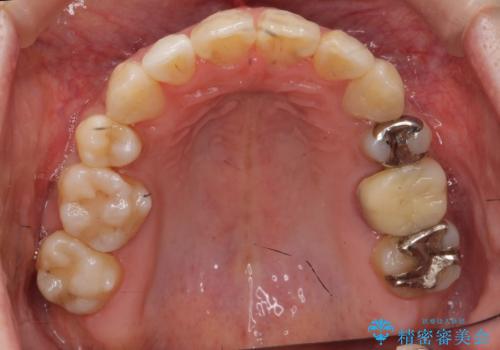

歯の移動量が大きく、また、少し歯も動きにくかったため矯正治療に時間はかかりましたがしっかり並べて前突感も大きく改善しました。

上の前歯が出ていた為、しっかり口を閉じることが難しい状態でしたが、楽に閉じられるようになりました。

側貌(横顔のライン)が治療前には下顎が後退したような状態が、口元を引っ込めたため相対的にしっかり前に出て見えるようになり、大きく改善しています。